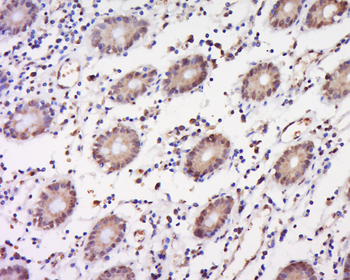

IF, IHC-Fr, IHC-P, WB

IF, IHC-Fr, IHC-P, WB

IF, IHC-Fr, IHC-P, WB

50 μl, 100 μl - KLF4 Recombinant Rabbit Monoclonal Antibody [orb608075]Featured

FC, ICC, IF, IHC-Fr, IHC-P, WB

IF, IHC-Fr, IHC-P, WB

FC, ICC, IF, IHC-Fr, IHC-P, WB

FC, ICC, IF, IHC-Fr, IHC-P, WB

FC, IF, IHC-Fr, IHC-P, WB